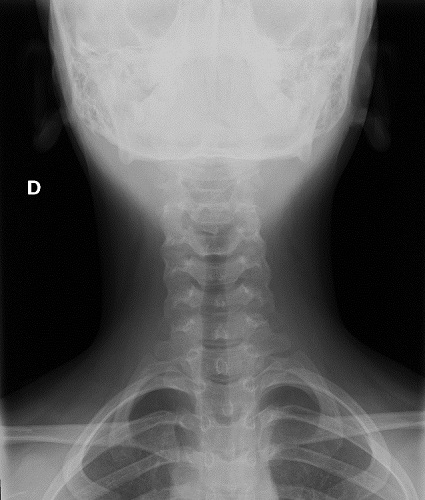

Se solicita radiografía cervical, con hallazgo de aumento de atenuación de partes blandas a nivel laterocervical izquierdo en la proyección anteroposterior (Fig. 1), que no se ve en la proyección lateral, presentando por lo demás una correcta alineación de la columna cervical sin líneas de fractura. Se consulta con el servicio de Radiología, que informa de que se trata de posible imagen artefactual debido a que el cabello está colocado sobre ese hombro. Se repite al día siguiente la radiografía con el pelo recogido, desapareciendo dicha imagen (Fig. 2).

Figura 2. Radiografía cervical con el cabello recogido